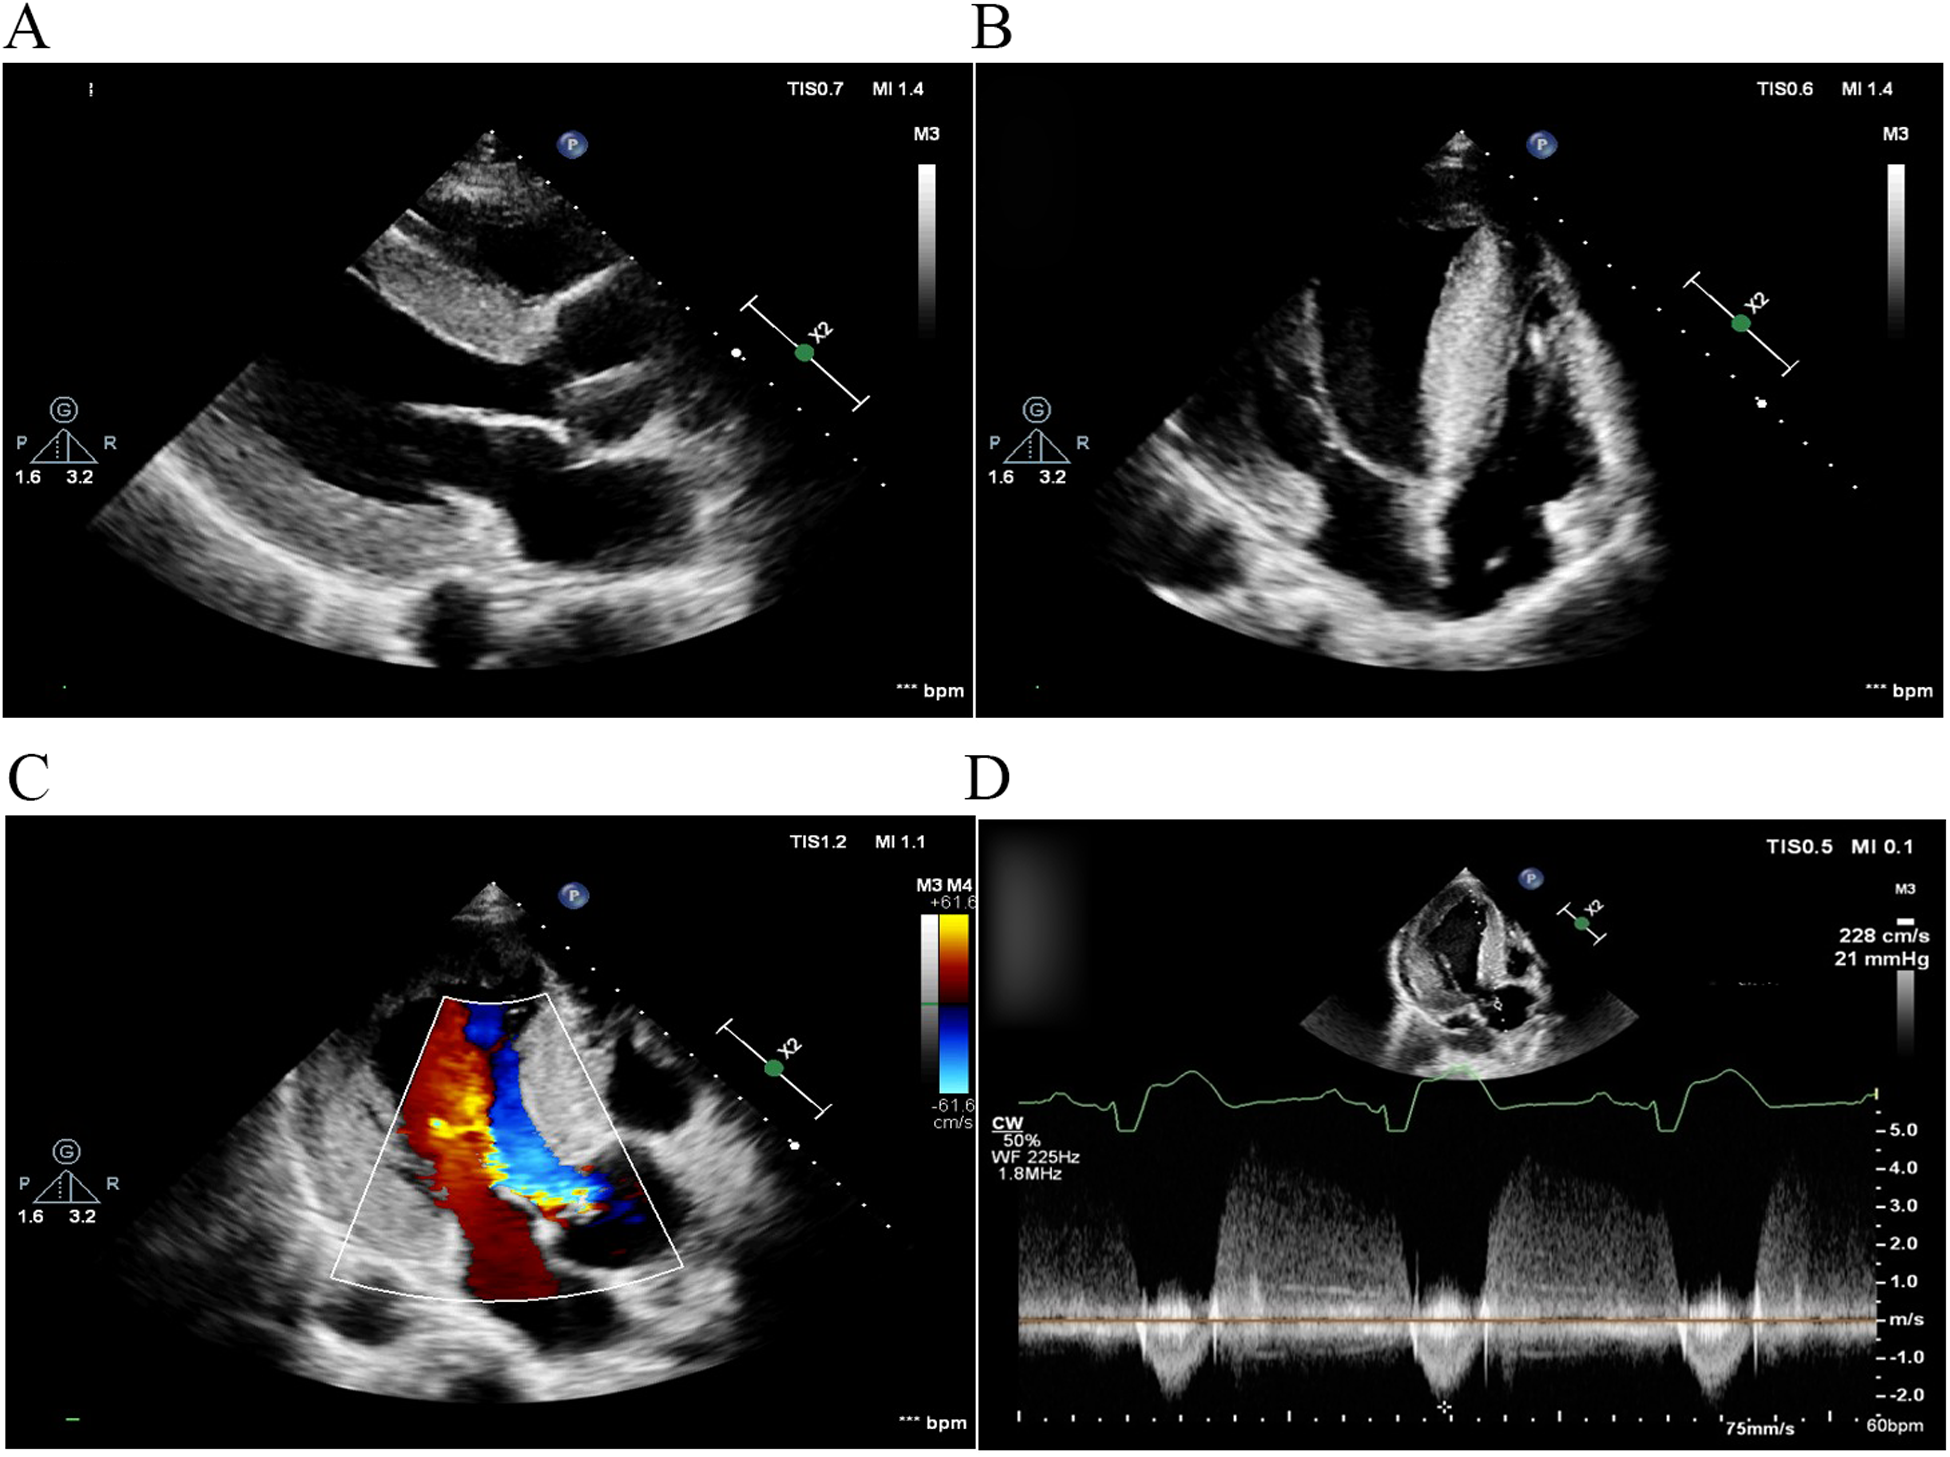

Two months later, left ventricular outflow tract dredging was performed to alleviate symptoms in the hospital. A permanent pacemaker was implanted due to complete atrioventricular block that occurred as a complication of the surgery. The patient's symptoms resolved, and the resting gradient decreased to 21 mmHg on follow-up TTE 1 month later (Figure 2).

Figure 2

TTE 1 month after left ventricular outflow tract dredging. (A) Parasternal long-axis view of the left ventricle and (B) apical four-chamber view. The diastolic interventricular septal thickness decreased to 22 mm. (C) Color Doppler flow imaging and (D) continuous wave Doppler demonstrated that left ventricular outflow tract obstruction was alleviated, with a peak gradient reduced to 21 mmHg. TTE, transthoracic echocardiography.